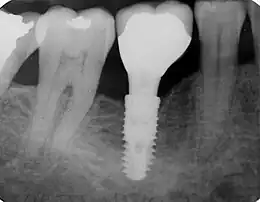

Molaire sur implant dentaire.

Un implant dentaire ou ancrage dentaire est un dispositif médical  sorte de vis en titane ou zircone ou polymère  inséré dans le maxillaire ou la mandibule et destiné à créer un ancrage capable de recevoir une prothèse dentaire amovible ou fixée[1].